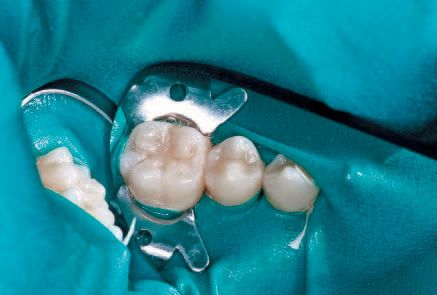

No local anesthesia is necessary, but rubber dam isolation is recommended to assist in the success of the ICON resin infiltration procedure. Cleanse the isolated tooth with NaOCl or Consepsis and rinse thoroughly with a water spray and air dry. The teeth are separated using one of the enclosed plastic wedges, which will allow for the placement of the Proximal-Tip foil matrix delivery system. The wedge can be maintained interproximally during the entire procedure if necessary (Fig. 5).

Screw one of the Proximal-Tips onto the end of the ICON-Etch (15% HCl), insert it between the teeth with the green side facing the affected proximal lesion, and turn the shaft 1½ to 2 turns to deliver the etchant. Leave the ICON-Etch on the surface for 2 minutes (Fig. 6).

Screw one of the Proximal-Tips onto the

end of the ICON -Etch (15% HCl), insert it between the

teeth with the green side facing the affected proximal

lesion, and turn the shaft 1 ½ to 2 turns to deliver

the etchant (Fig. 6).